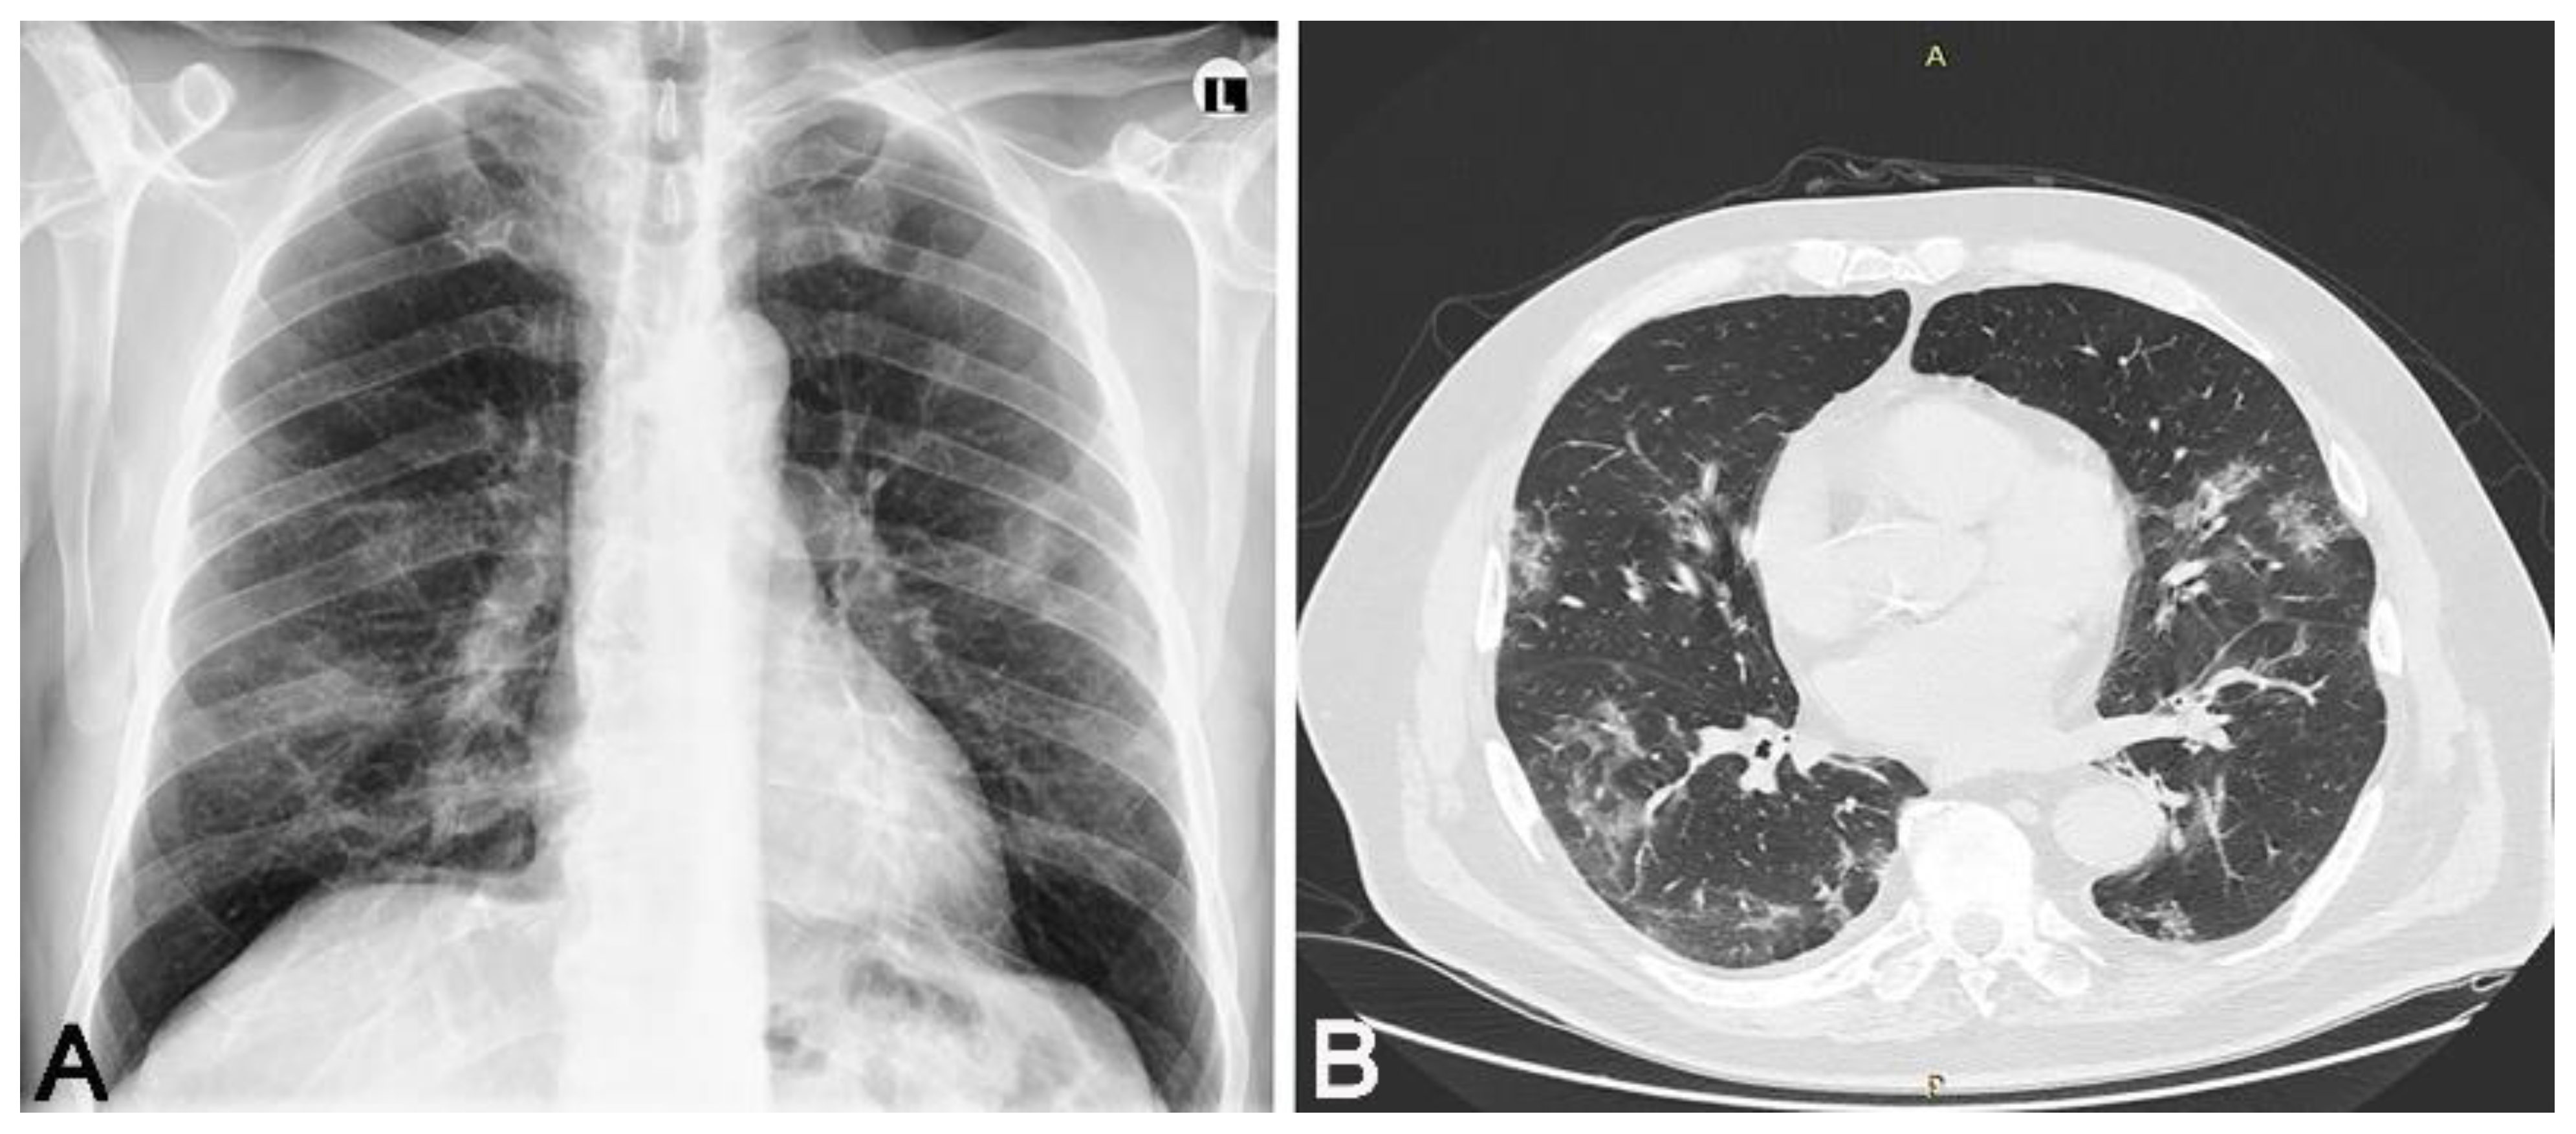

We conducted a cross-sectional observational study. We received informed consent from each participant. This study was conducted after obtaining permission from the local ethics committee. We had two groups of participants who overcame the SARS-CoV-2 infection; the diagnosis was confirmed by a positive result of a real-time reverse PCR test by nasal/pharyngeal swabs. In the first group of 16 participants, there were patients who overcame a mild form of the disease, and in the second group, there were 23 patients who overcame a moderate form of the disease. All patients who had a mild form of the disease had a normal X-ray of the lung, and patients with a moderate form of the disease had unilateral or bilateral pneumonia proven by MSCT. The group that overcame unilateral or bilateral pneumonia (Figure 1, Figure 2 and Figure 3) treated with antibiotic therapy, but without corticosteroid therapy, differed from the second group of participants, who had a mild form of disease.

Figure 1. Thirty-eight-year-old male patient without any chronic diseases was admitted to the emergency department as a SARS-CoV-2 positive with high fever, cough, dyspnea and fatigue. Chest X-ray showed (A) bilaterally gentle inhomogeneous shading initial infiltrative changes. After 9 days from the onset of infection, dyspnea worsened, chest MSCT showed (B) areas of enhanced attenuation by the type of ground glass, and patchy consolidations are seen on both sides. The patient developed bilateral pneumonia. Legend: L—left side, small A letter on panel B: A—anterior, P—posterior.